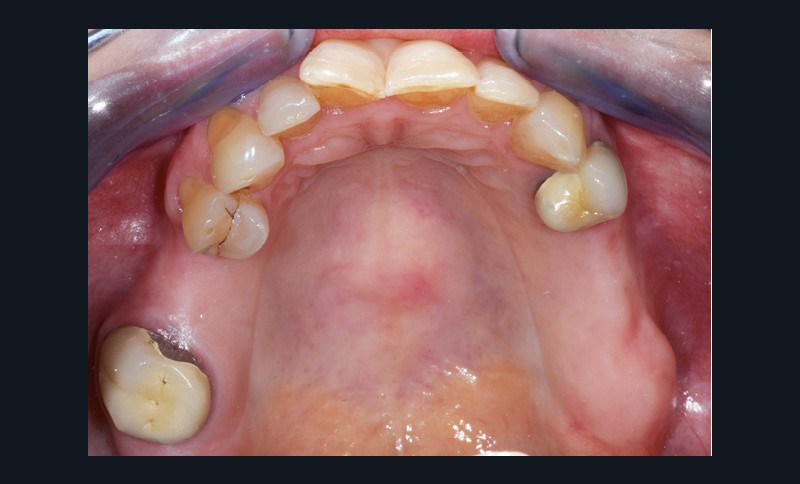

Une patiente d’une cinquantaine d’années consulte pour refaire sa prothèse amovible partielle métallique maxillaire, source d’inconfort (fig. 1 et 2).

Nous sommes en présence, au maxillaire, d’un édentement de classe 2 subdivision 1 de moyenne étendue (fig. 3). La problématique propre à ce cas de classe 2 est le soulèvement lors de la mastication d’aliments mous/collants et l’asymétrie. Cependant, la présence d’une subdivision compense en partie l’asymétrie. La recherche d’appuis les plus antérieurs possible à l’axe de rotation pour contrer le mouvement de soulèvement postérieur est également…